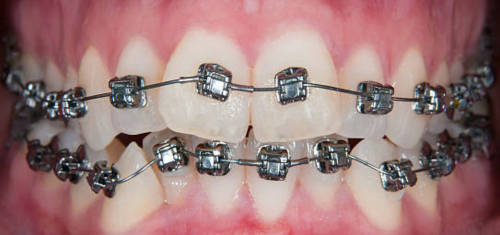

Before / After

From stained or misaligned teeth to a radiant, confident smile, our results speak for themselves. See the difference professional dental treatment can make — and imagine what we can do for you.

Braces & Invisalign